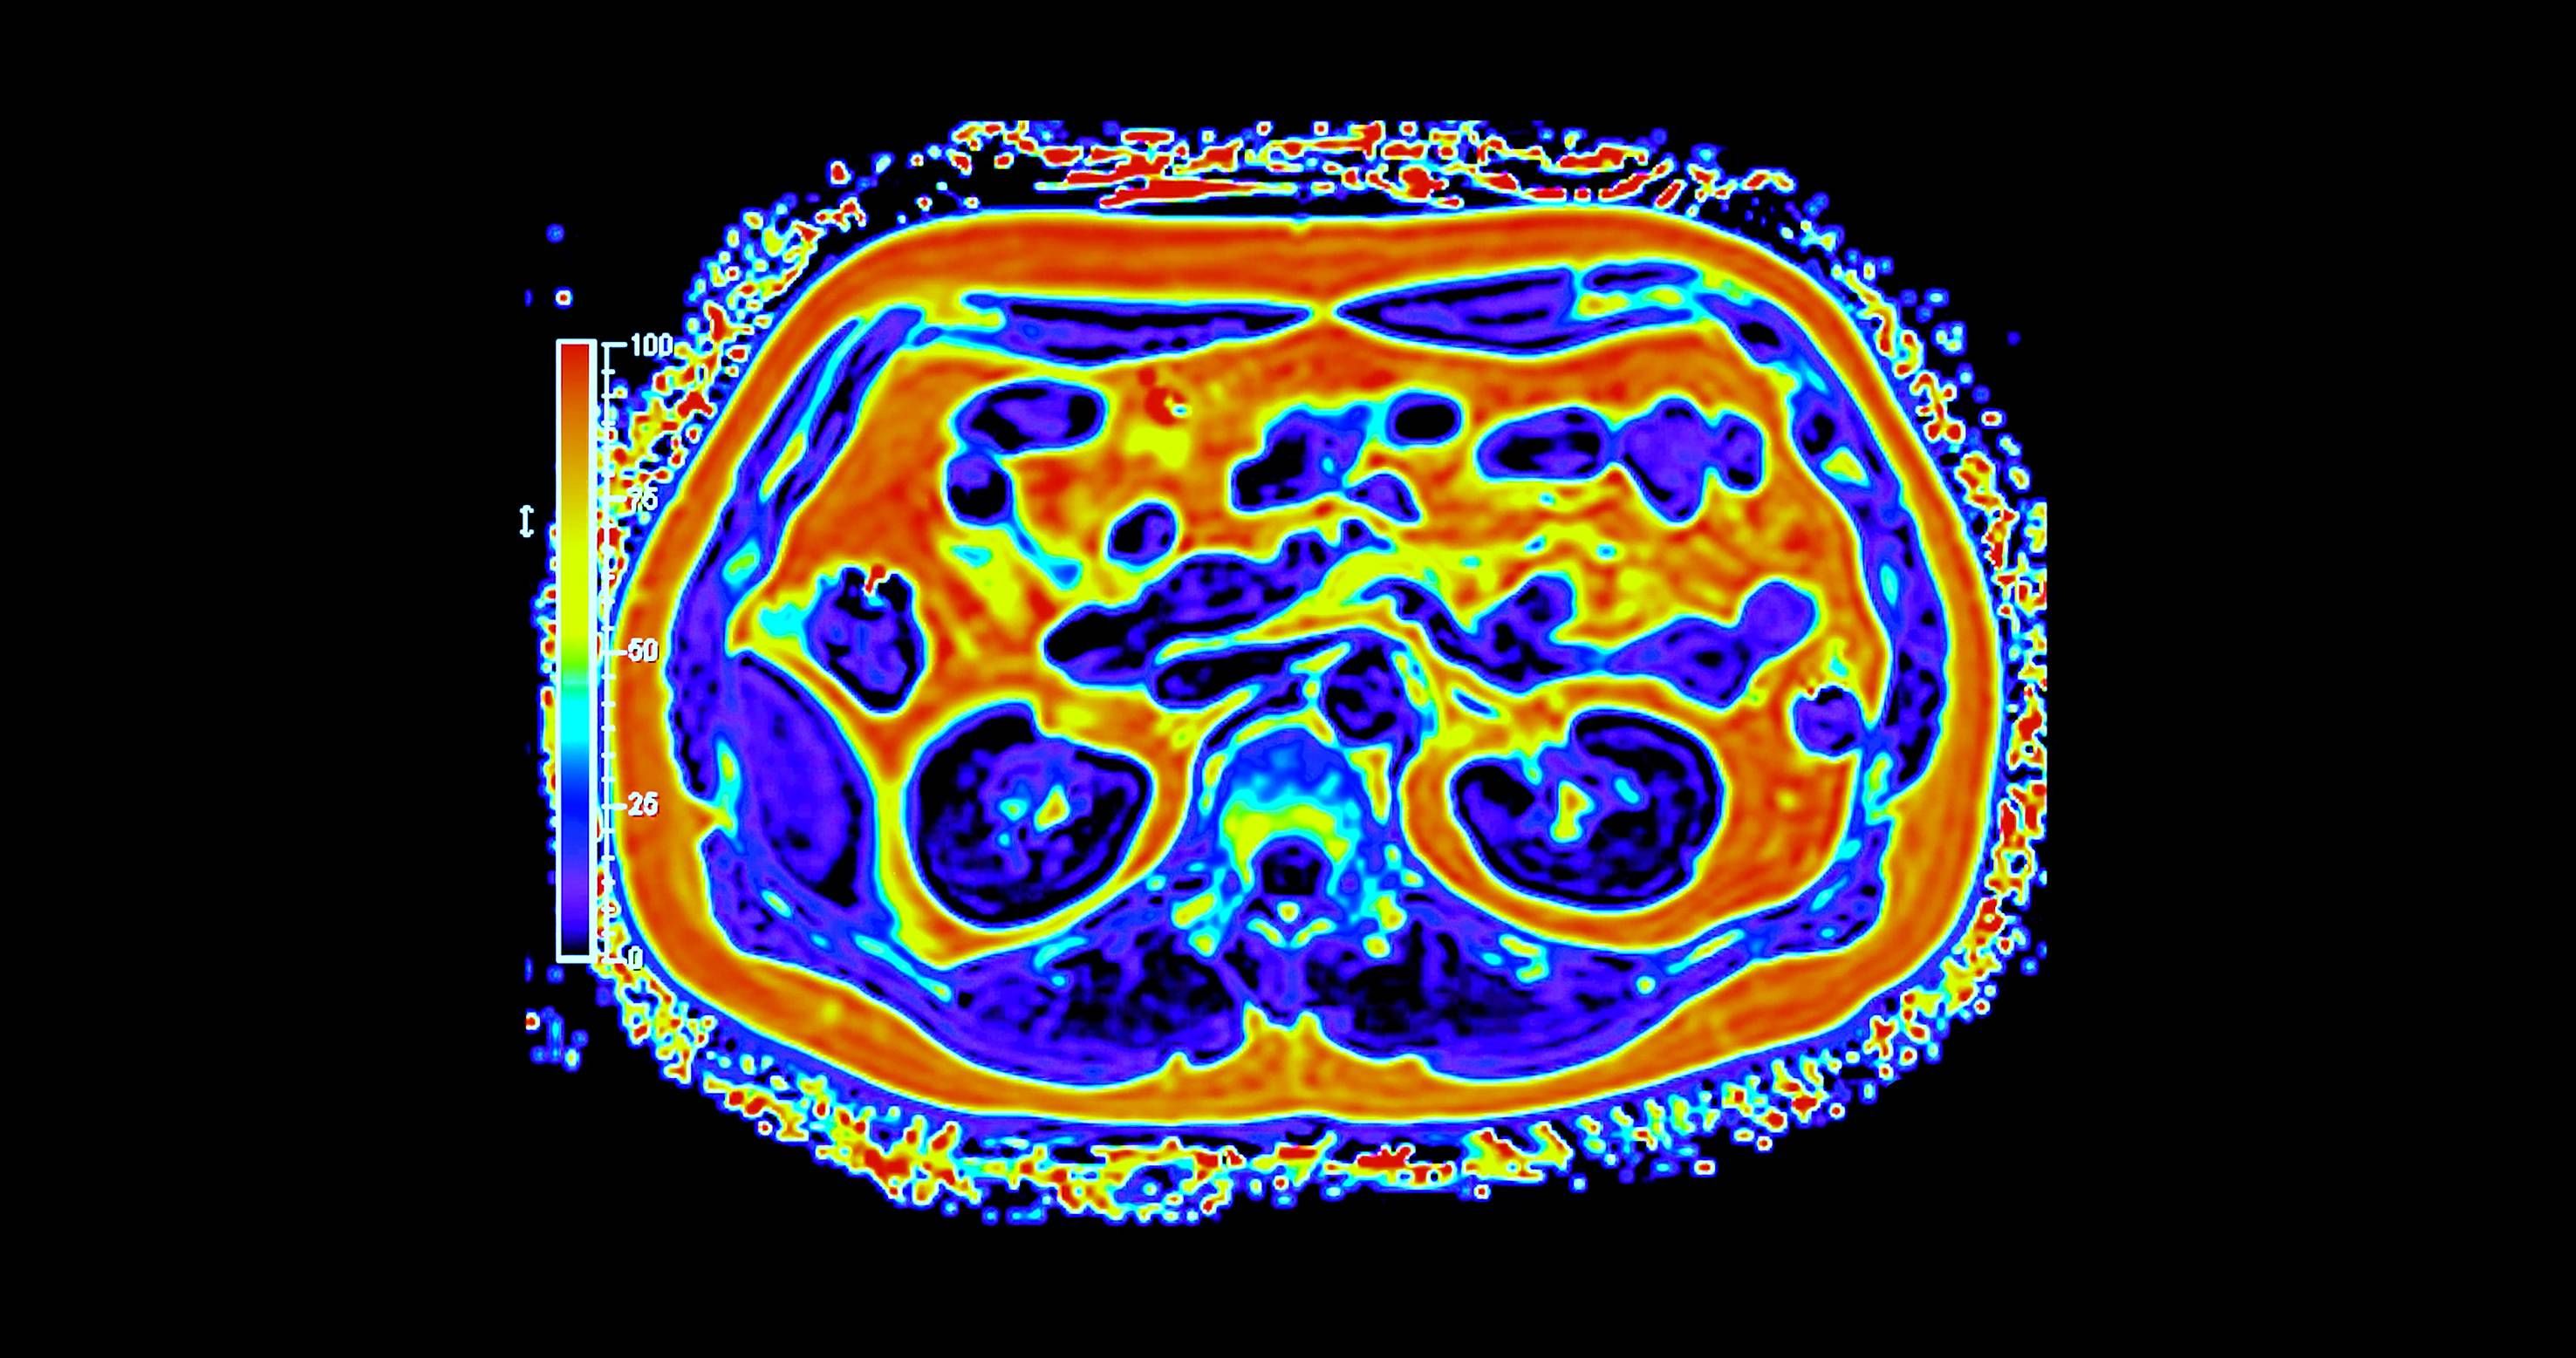

غالباً ما يُتناول تحوّل القطاع الصحي عبر محطات واضحة للعيان، مثل إنشاء مستشفيات جديدة، وإطلاق منصات رقمية، واعتماد أجهزة طبية متقدمة. غير أنّ جانباً أقل ظهوراً وأكثر حسماً يتمثل في بناء بنية تحتية تشخيصية قادرة على دعم الاكتشاف المبكر والطب الدقيق والرعاية الوقائية على نطاق وطني. ويقع التصوير الجزيئي، ولا سيما التقنيات الهجينة، مثل «PET - MRI» في صميم هذا التحول.

وعلى خلاف التصوير التقليدي، يجمع التصوير الجزيئي بين التفاصيل التشريحية والبيانات الوظيفية الآنية، ما يتيح للأطباء رؤية كيفية عمل الأنسجة لا مجرد شكلها. وفي مجالَي الأورام والأمراض العصبية، قد يُحدث هذا الفرق تحولاً في توقيت الاكتشاف أو في تعديل خطط العلاج أو في تجنّب إجراءات غير ضرورية. غير أن توسيع هذه القدرات عبر بلد واسع ومتنوّع جغرافياً يطرح تحديات تتجاوز كثيراً مجرد اقتناء الأجهزة.

أحرزت السعودية تقدماً تدريجياً في نشر أنظمة التصوير المتقدم، بما في ذلك «PET - CT» و«PET - MRI» داخل مراكز طبية كبرى. وبحسب الدكتور سامح الشيخ المدير العام لشركة التصوير الجزيئي والقطاع الطبي بوادي جدة، أثبتت هذه التقنيات قيمتها السريرية عبر الكشف عن انتشار سرطاني أو اضطرابات لم تُظهرها وسائل التصوير التقليدية، ما أتاح تعديل العلاج فوراً في عدد من الحالات.

لكن التركيز على المعدات وحدها قد يُبسّط المشكلة أكثر من اللازم؛ فالتصوير الجزيئي يعتمد على منظومة متكاملة تشمل إنتاج المستحضرات الصيدلانية الإشعاعية، وكوادر بشرية عالية التخصص، وإدارة آمنة للبيانات، ومسارات إحالة منسّقة.